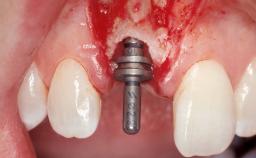

A 30-year-old female patient had lost tooth 21 and was referred to our clinic for consultation and treatment. Due to advanced apical infection, tooth 21 had been extracted two months earlier at another clinic and an acrylic-resin tooth had been bonded to the adjacent teeth. The patient desired implant treatment to avoid any damage to the adjacent natural teeth. While the patient had no history of any systemic disorder, she was a heavy smoker and exhibited medium to advanced periodontitis in the entire jaw. After the initial treatment to achieve a pocket probing depth of less than 4 mm and no bleeding on probing, a decrease in the height of the papillae mesial and distal to the extraction site and overall gingival recession were observed.

Type of Implants One-Piece|Reduced-Diameter

Bone Augmentation Horizontal|Staged

Augmentation Materials Autogenous chips|Membrane

Bone Volume Deficient horizontally, requiring prior grafting